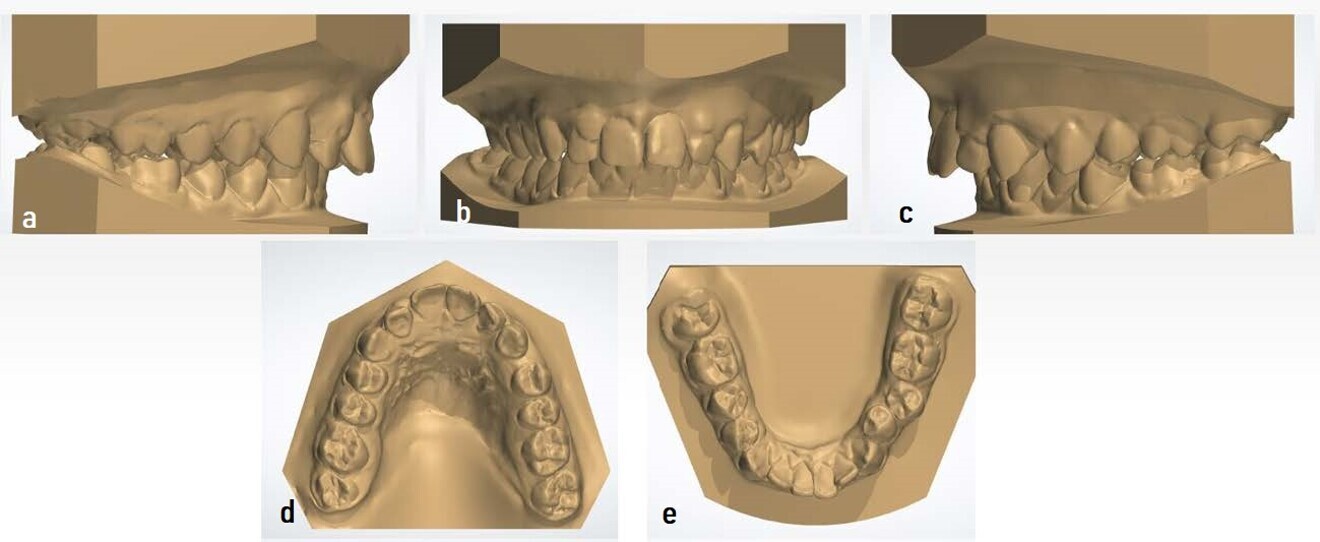

Figs. 12a–e: Digital models taken after removal of the Class II Carriere Motion Appliance.

After a few months, owing to the canine extrusion caused by the elastics, we had to change the position of the distaliser to the maxillary left premolar and consequently placed the button on tooth #37 to increase the distance of the elastic. For the maxillary right quadrant, the canine situation did not require any changes. At this stage of treatment, 8 oz elastics were used (Fig. 10). This device was used for a total of seven months, in which time a Class I molar overcorrection was intentionally obtained (Fig. 11) in case of possible relapse. The study models were taken after removal of this appliance (Fig. 12).